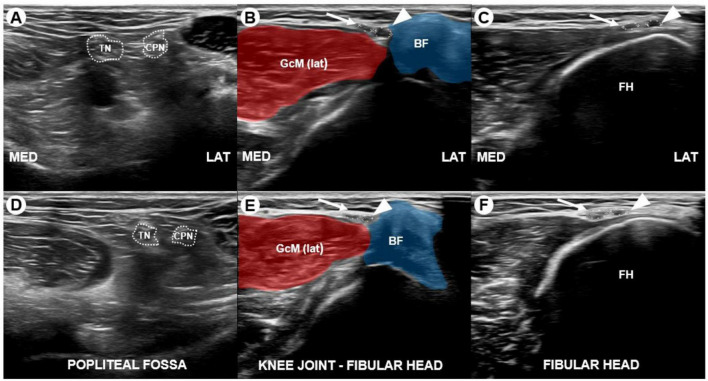

Prolonged squatting is a well-documented cause of common peroneal neuropathy, wherein the common peroneal nerve is thought to be compressed between the biceps femoris tendon and the lateral head of the gastrocnemius muscle or the fibular head. However, deep peroneal neuropathy resulting from prolonged squatting has not been previously reported. We present the case of a tile installer who developed unilateral deep peroneal neuropathy following extended squatting, diagnosed through ultrasonography, which identified the bilateral division of the common peroneal nerves between the knee joint and the fibular head. This case underscores the value of ultrasonography, particularly when electrodiagnostic results are inconsistent with clinical expectations.